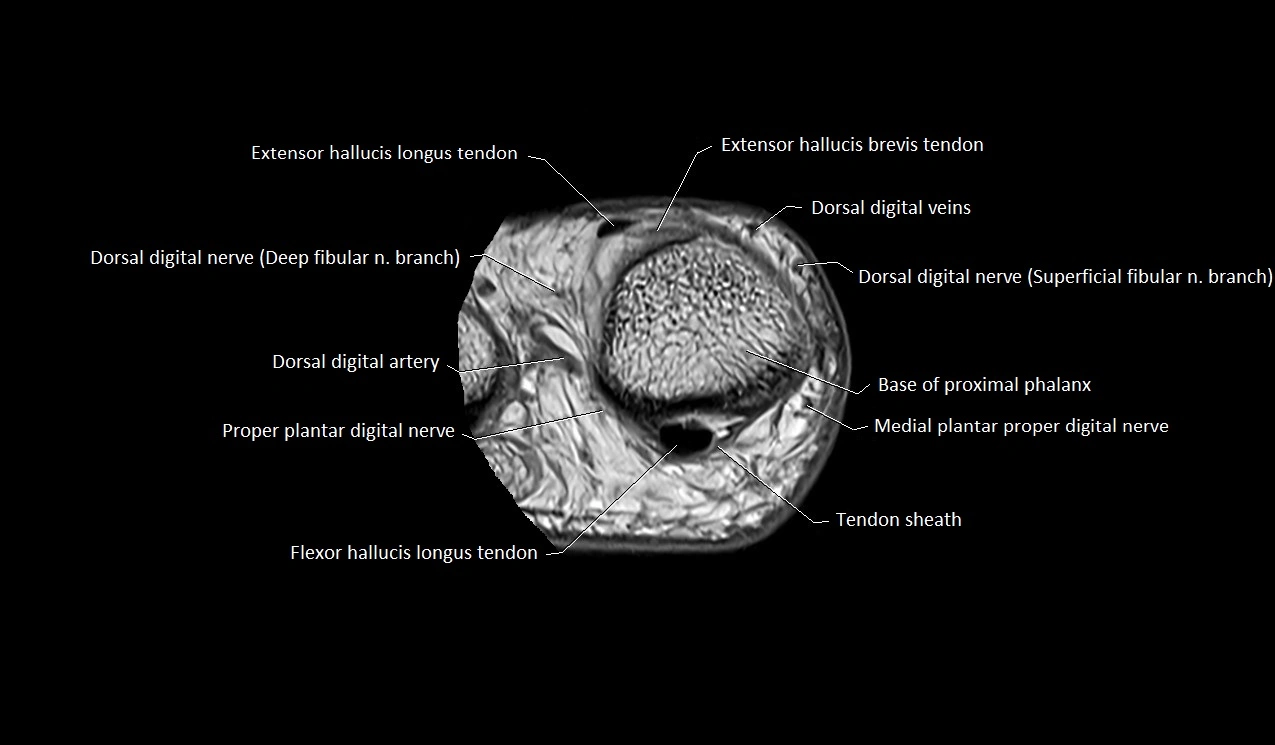

MRI image

image